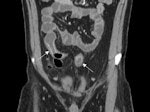

Patient with active ileocolonic Crohn's disease.

Small-bowel imaging guides therapeutic management of Crohn's disease by informing the clinician about the location, extent, and activity of pathology, according to Dr. Sam Stuart, a radiologist with Royal Free Hospital in London. Imaging aids diagnosis, monitors progression, assists treatment, and identifies small-bowel strictures that may need surgical resection.

CT enterography (CTE) has largely replaced small-bowel follow-through as the imaging modality of choice for Crohn's disease. Its popularity stems from its ability to noninvasively investigate extraintestinal effects of inflammatory small-bowel disease located outside the reach of x-ray barium imaging.